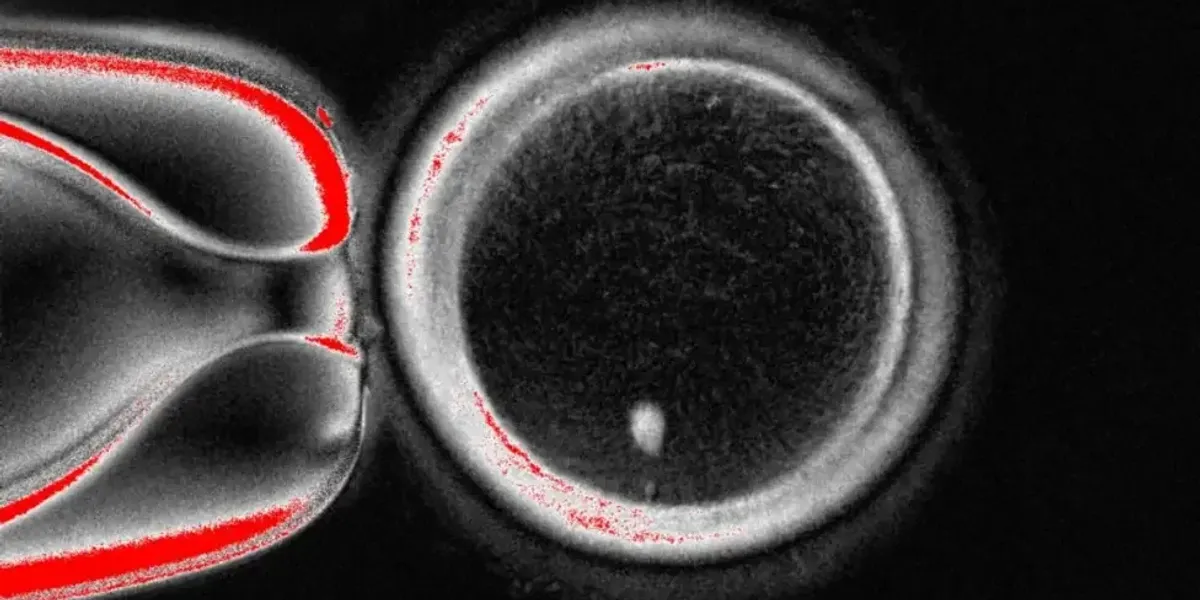

The large circle is the egg viewed under a microscope

|OHSU